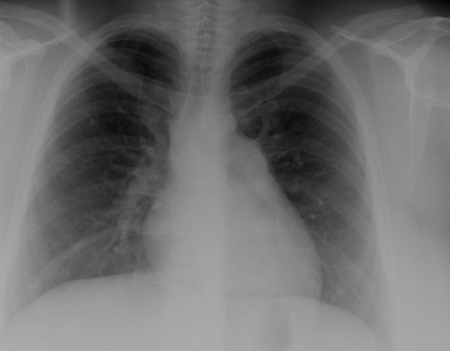

A radiografia torácica e o eletrocardiograma (ECG) podem estar normais nos DSVs. Nos defeitos maiores, há cardiomegalia e aumento das marcas vasculares pulmonares na radiografia torácica, e o ECG revela hipertrofia do ventrículo esquerdo; a hipertrofia do ventrículo direito pode ocorrer em defeitos maiores. Os DSVs de entrada estão associados ao desvio do eixo esquerdo no ECG. A ecocardiografia fornece informações importantes sobre a anatomia do defeito, o volume do desvio circulatório e a pressão do ventrículo direito.[25][26][Figure caption and citation for the preceding image starts]: Radiografia torácica demonstrando a transposição circulatória pulmonarMayo Clinic Foundation [Citation ends].